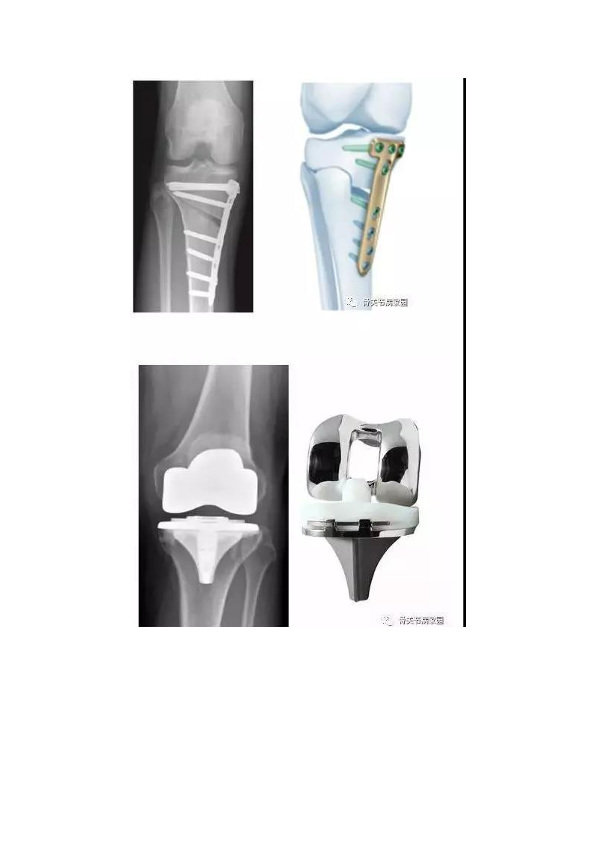

胫骨高位截骨术